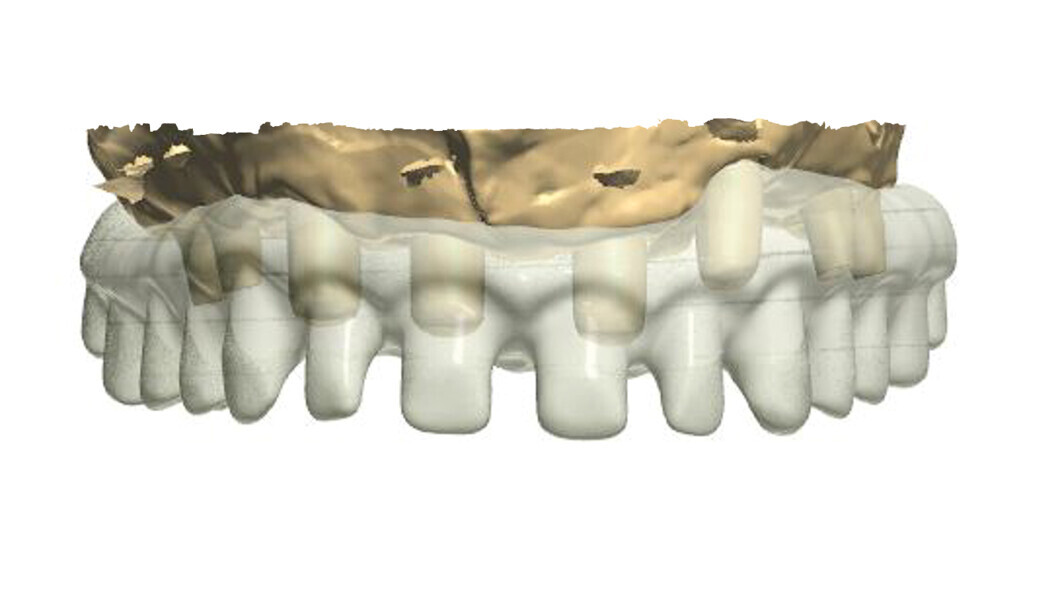

Fig. 2: Design of the construction with the transparency mode on.